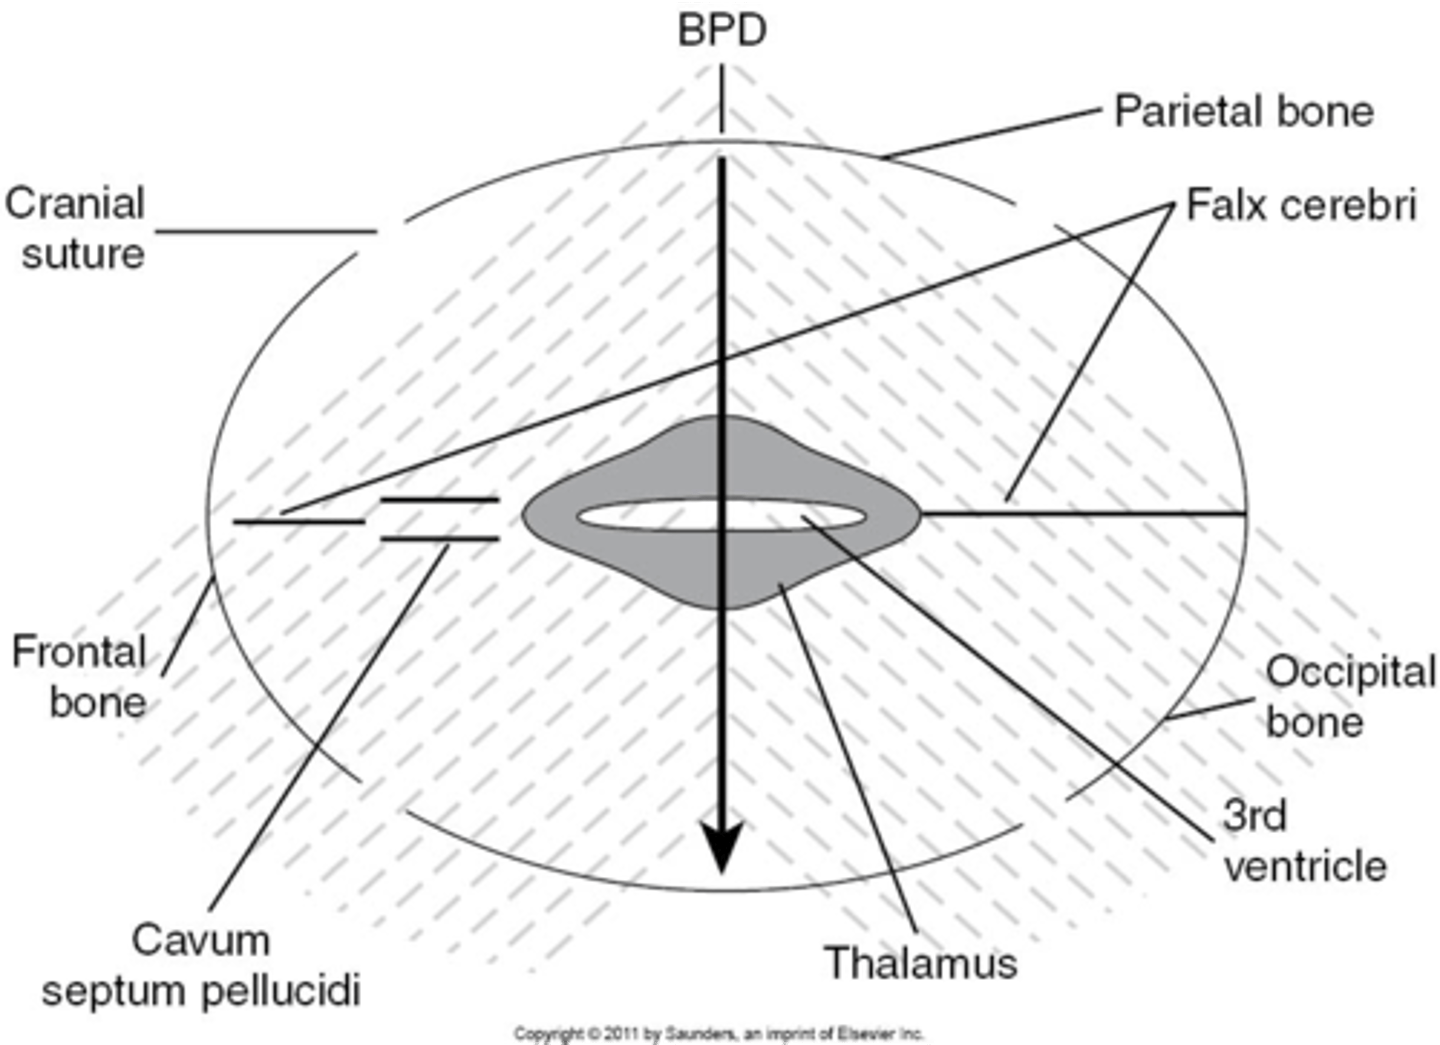

What is the most widely accepted means of measuring fetal head and estimating fetal age?

BPD

What part of the skull do you measure BPD?

midline echo complex

How do you find midline echo complex on ultrasound?

move the transducer caudally from lateral ventricles

When measuring BPD, paired ___ will be seen on either side

thalamus

When measuring BPD, what is located between the thalamus?

3rd ventricle